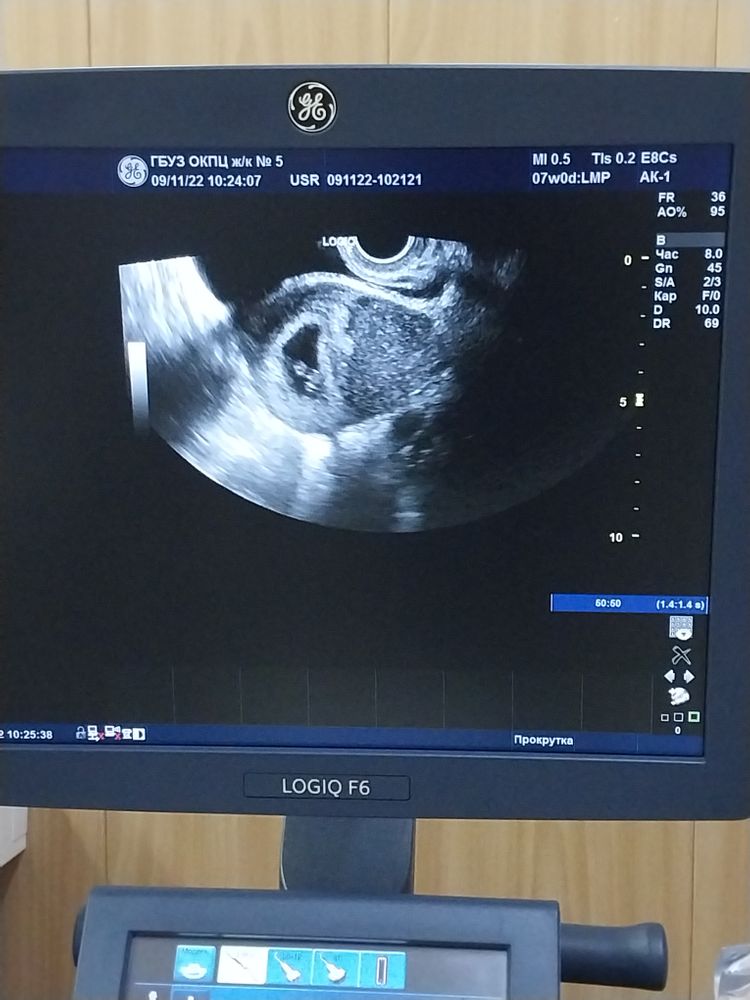

Все хорошо, это мозг. Я задала такой же вопрос в 7 недель, испугалась, мне сказали так формируется мозг. вот чёрное пятно, это место мозга Изображение

Дарья Тарасенко, моё узи на 7 недель Изображение